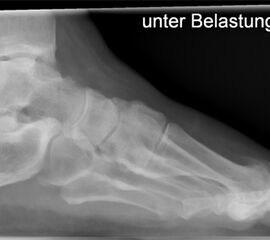

• Belastete Röntgenaufnahmen in 3 Ebenen.

• Evtl. Fotodokumentation der Exostosen.